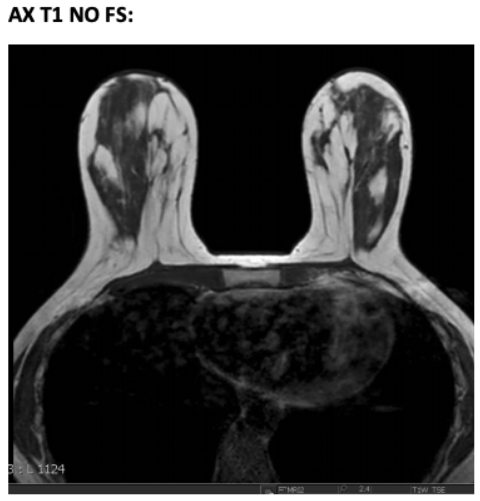

AX T1 NONE FOV to cover both breasts Center on both breasts, FOV to cover entire breast tissue and lymph nodes.

MR Breast AX T1